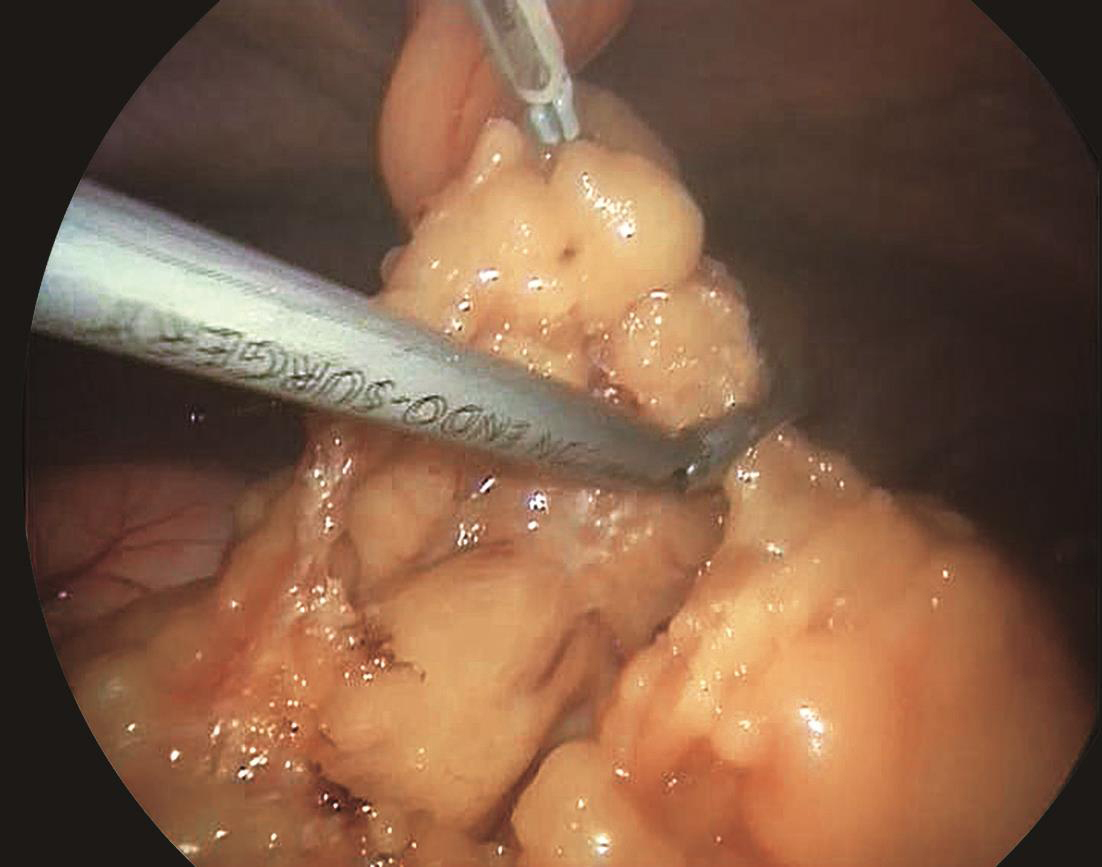

患者取平卧位,头高脚低,四孔或三孔法操作;首先自胃网膜血管弓下方横行打开胃结肠韧带(图6-1),探查胰腺颈、体、尾,必要时可打开胰腺下缘被膜,游离胰腺后方深入探查;清楚定位肿瘤后,镜下缝合肿瘤一针作为牵引用(图6-2),超声刀紧贴肿瘤,完整剜除;检查胰腺创面,选择性缝合创面(图6-3);取出标本,送冰冻,留置引流,关闭腹壁切口,术毕(图6-4)。

图6-2 定位肿瘤后,缝合肿瘤后牵引肿瘤